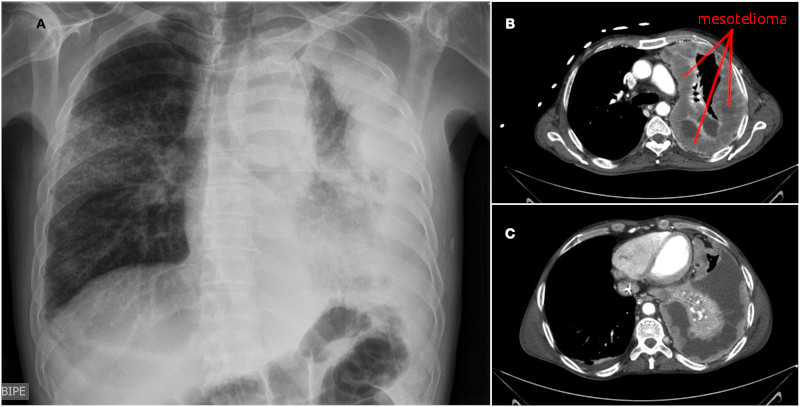

Mesotelioma

- Descrizione: Secondo la MU il mesotelioma è una neoplasia che origina dal mesotelio, lo strato di cellule che riveste le cavità sierose del corpo: Pleura, Peritoneo, Pericardio, cavità vaginale dei Testicoli. La quasi totalità dei casi attualmente rilevati del tumore si riferisce a mesotelioma pleurico, ed è correlata all'esposizione alle fibre aerodisperse dell'amianto (asbesto), con una latenza temporale particolarmente elevata - 15-45 anni - e un decorso di 1-2 anni.